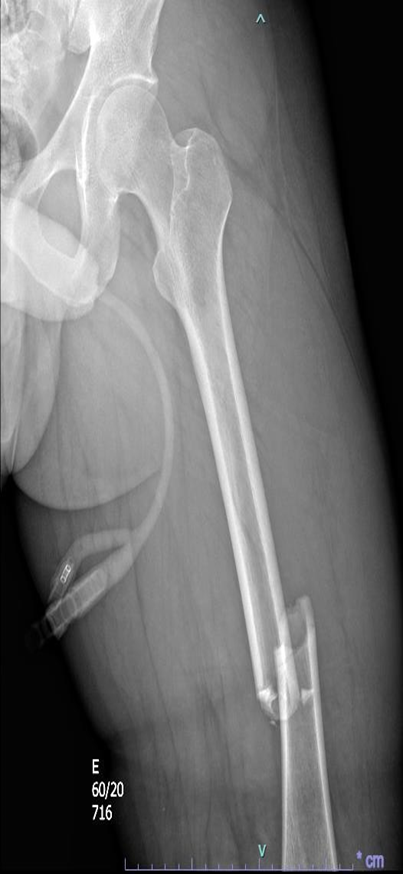

Paciente do sexo masculino, 24 anos, da entrada no pronto-socorro do Conjunto Hospitalar de Sorocaba (CHS) dia 01/04/2025, vítima de colisão moto x anteparo fixo, apresentando fratura exposta de fêmur esquerdo, rotação externa de membro inferior direito com fratura exposta de fêmur direito distal e desalinhamento de antebraço esquerdo.

Frente ao caso, como conduta inicial foram solicitadas radiografias de tórax e pelve no leito, iniciada expansão volêmica com 500 mL de Ringer lactato (apresentando resposta com melhora da PA: 128×71 mmHg e FC 105 bpm), radiografia de fêmur bilateral, joelho bilateral, perna bilateral, braço e antebraço esquerdo, tomografias de crânio, face, coluna cervical, torácica e lombar, tórax, abdome e pelve, sendo as duas últimas com contraste. Além dos exames de imagem, foram solicitados também exames de laboratório.

Figura 3: radiografia de fêmur direito.

Figura 4: radiografia de fêmur esquerdo.

O paciente foi abordado cirurgicamente de urgência pela equipe de ortopedia, realizado fixador linear de fêmur esquerdo, fixador transarticular de joelho direito e tala axilo palmar esquerda permaneceu internado em unidade de tratamento intensivo (UTI) para observação e cuidados intensivos, na admissão recebeu transfusão de dois concentrados de hemácias (CH) e duas bolsas de plasma fresco congelado (PFC) e iniciado antibioticoprofilaxia com amicacina e cefazolina.

No dia 12/04/2025 paciente foi reabordado pela equipe de ortopedia para realização de osteossíntese de fêmur esquerdo com haste retrógrada.